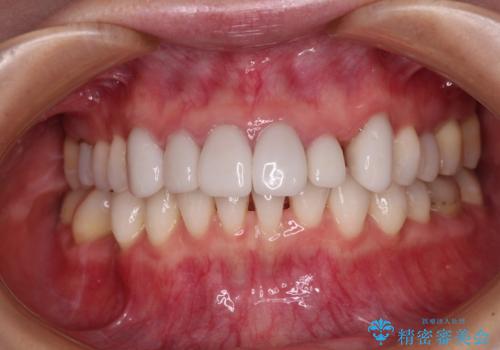

前歯のデコボコと奥歯の咬み合わせをインビザラインで改善

- 上下前歯のデコボコと奥歯の欠損を気にして来院された患者様です。

右下の欠損分は奥歯が倒れ込んでスペースがなくなっていたため、矯正治療により本来の位置に歯を移動させ、オールセラミックブリッジによる欠損補綴治療を行うこととしました。

全顎的にセラミッククラウンが多く装着されているため、インビザラインによる矯正治療を行うこととしました。

右下は移動量が多いため、十分な移動が達成されない場合はワイヤー装置を使用する予定としておりましたが、しっかりとマウスピースを装着してくださったため、前歯とともに十分に歯を動かすことができました。